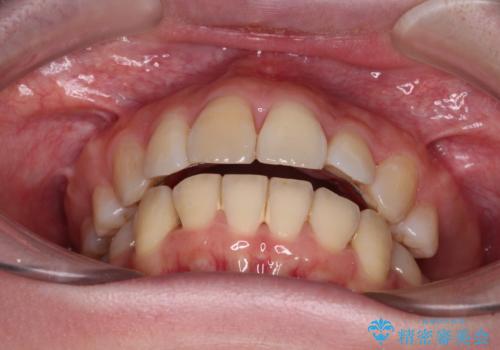

上下前歯をワイヤー保定していましたが、強い舌の突出癖により上下ともにスペースができ、上下前歯は非接触になっていました。

舌の突出癖を改善したことで、突出感のあった口元の印象も、やや引っ込めることができました。